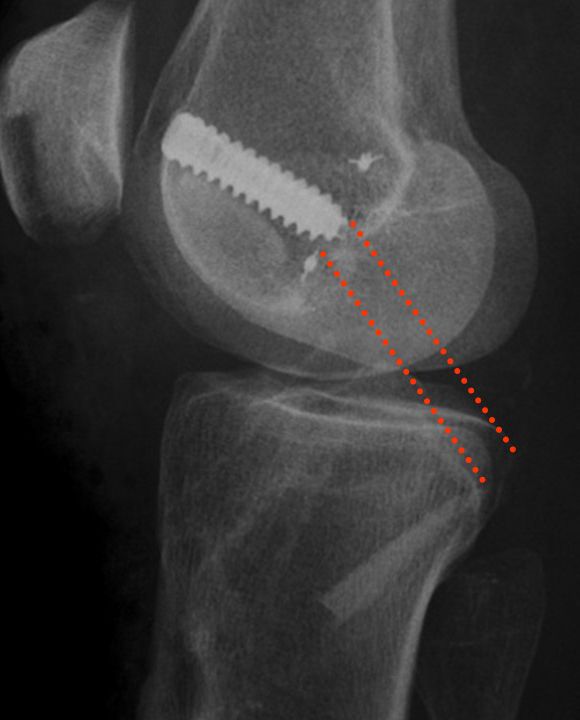

The Indication for operative treatment is based on the amount of posterior translation (borderline according to literature 8 mm) and the additional peripheral instability, which leads to increased posteromedial or posterolateral rotational instability. The indication goes along with the degree of increased rotatory instability and malalignment (Fig 3).

Fig 3 - Radilogical Documentation of Chronic PCL Instability